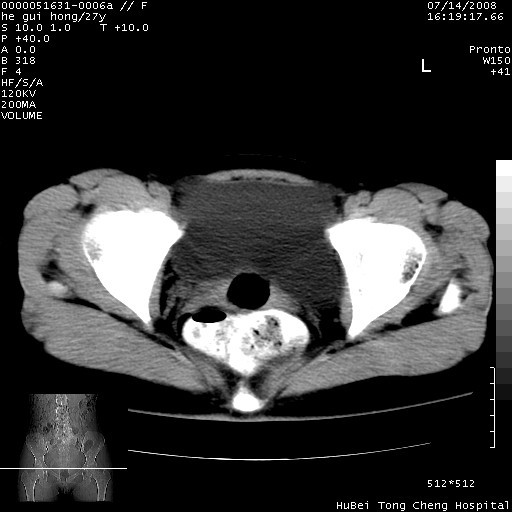

以下是引用杀毒软件在2008-7-20 8:03:00的发言:[br]支持双侧卵巢囊腺瘤可能性大!

以下是引用zjzjr在2008-7-20 13:36:00的发言:[br]双侧附件囊腺瘤可能性大!